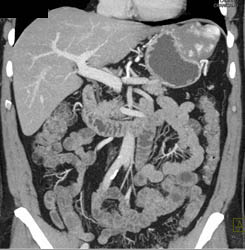

Hepatic Hemangioma Simulates A GIST Tumor of the Stomach- See Full Sequence of Images